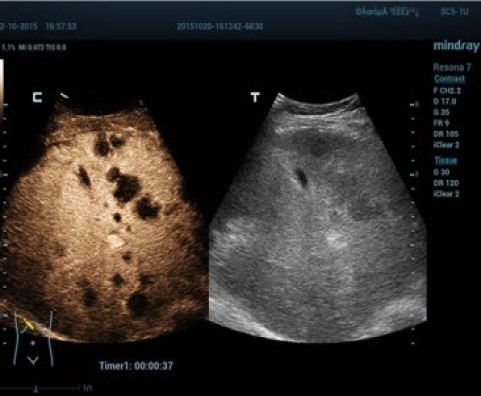

Эластография Sound Touch

Контрастная эхография лимфомы печени